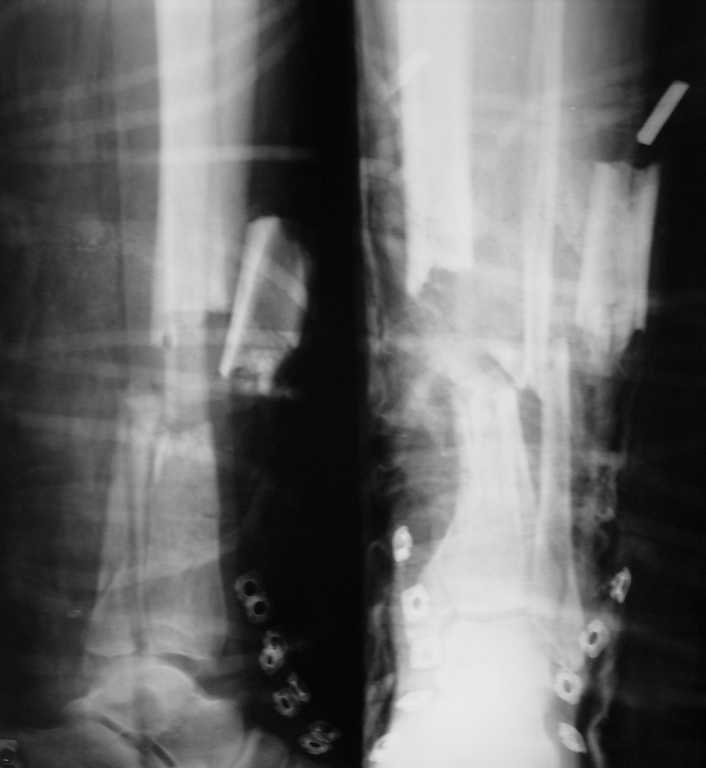

открытый многооскольчатый перелом костей голени

больной 38 лет, бытовая травма, доставлен через 30 мин после травмы.

Уважаемый Руслан! Мало подробностей механизма травмы. Судя по снимку, смею предположить, что травма, однако, высокоэнергетическая, т.к. промежуточный отломок б/берцовой "улетел" далеко. Если это так, то питание его скорей всего нарушено, если не отсутствует совсем. Как ни печально, его придется "выкинуть". Я бы сделал так: хир. обраборка раны(если таковая есть), аппарат внешней фиксации (в нашем случае это был бы Илизаров, хотя возможны и варианты). Наложил бы с прицелом на дальнейший костный транспорт . Повреждения в области голеностопа синтезировал бы открыто в "одну сессию" с аппаратом - винтами или спицами с напайками к этому же аппарату. Далее по показаниям повторные хир. обработки, дренирование и т.п. В любом случае какое-либо "железо" в зону диафизароного перелома пока ставить бы не стал. Вопрос о закрытии возможных ран: путем временного "острого укорочения" сегмента - это если кожи не хватает, различные виды кожной пластики .... Да выложите снимки кожных покровов, если возможно, а то все одни предположения... Удачи. Станислав Дмитриев. Н.Новгород.

Общеизвестно, что выбор вида остеосинтеза открытых переломов длинных костей в первую очередь зависит от типа открытого перелома то есть от степени повреждения мягких и костной ткани, сосудистого и нервного пучка, а самое главное качество первичной хиругической обработки играет решаюшую роль. К сожалению, в Вашем случае не указан тип открытого перелома, согласитесь если III-IV тип открытого перелома, то погружные виды остеосинтеза (особенно LCP) могут создать проблемы в течении открытого перелома, так как при локализации открытой фрактуры по медиальной поверхности вероятность развития некроза и образования дефекта тканей возрастает. Судя по рентгенологической картине, у Вашего пациента имело место высокоэнергичная травма, то что бытовая травма ничего не раскрывает, если можно конкретизируете пожалуйста обстоятельства травмы!

бЛАГОДАРЮ ЗА ОТВЕТ, УЧИТЫВАЯ МОЙ НЕБОЛЬШОЙ ТРАВМАТОЛОГИЧЕСКИЙ ОПЫТ(2 ГОДА), ИНФОРМАЦИЯ В ОТВЕТАХ ОЧЕНЬ ПОЛЕЗНА.ЧТО КАСАЕТСЯ СОСТОЯНИЯ БОЛЬНОГО ПРИ ПОСТУПЛЕНИИ - СОСТОЯНИЕ УДОВЛЕТВОРИТЕЛЬНОЕ, СОЗНАНИЕ ЯСНОЕ, РАНА ПО НАРУЖНОЙ ПОВЕРХНОСТИ Н/3 ЛЕВОЙ ГОЛЕНИ С ПРИЗНАКАМИ КРОВОТЕЧЕНИЯ, РАЗМЕРЫ РАНЫ - 5Х10 СМ,КАППИЛЯРНЫЕ ПРОБЫ НА ПАЛЬЦАХ ЛЕВОЙ СТОПЫ - НАПОЛНЕНИЕ ОСЛАБЛЕНО,ПУЛЬСАЦИЯ СОСУДОВ НЕ ПАЛЬПИРУЕТСЯ,ИННЕРВАЦИЯ СОХРАНЕНА.ПОСЛЕ ПОДГОТОВКИ - В ОПЕРАЦИОННУЮ, ПОПЫТАЛИСЬ СДЕЛАТЬ ОТКРЫТУЮ РЕПОЗИЦИЮ, ВЫЛЕТЕВШИЙ ОСКОЛОК ПОСТАВИЛИ НА МЕСТО, НАЛОЖИЛИ иЛИЗАРОВА 4-МЯ КОЛЬЦАМИ.СНИМКИ И ФОТО ВЫЛОЖУ...